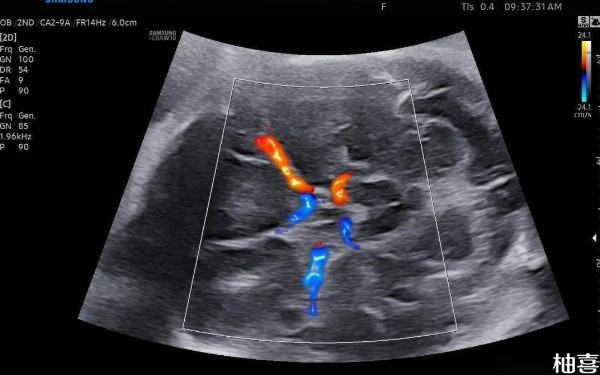

38周孕晚期的胎儿大脑中动脉彩超怎么看?

38周孕晚期的胎儿大脑中动脉彩超的数据有正常、偏高、偏低三种类型,其中胎儿大脑中动脉正常说明胎儿很好,如果偏高或偏低,也不用太担心,孕妇多注意胎动的情况,平时多吃豆制品,坚果、鱼,肉,鸡蛋,牛奶等食物,补充能量,保证胎儿能摄入充足的能量。一周后再去医院检查。